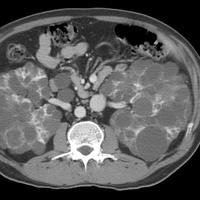

Диагностика объемных образований почек

Субъективные симптомы, такие как боль, гематурия и пальпируемая опухоль в поясничной области, являют...